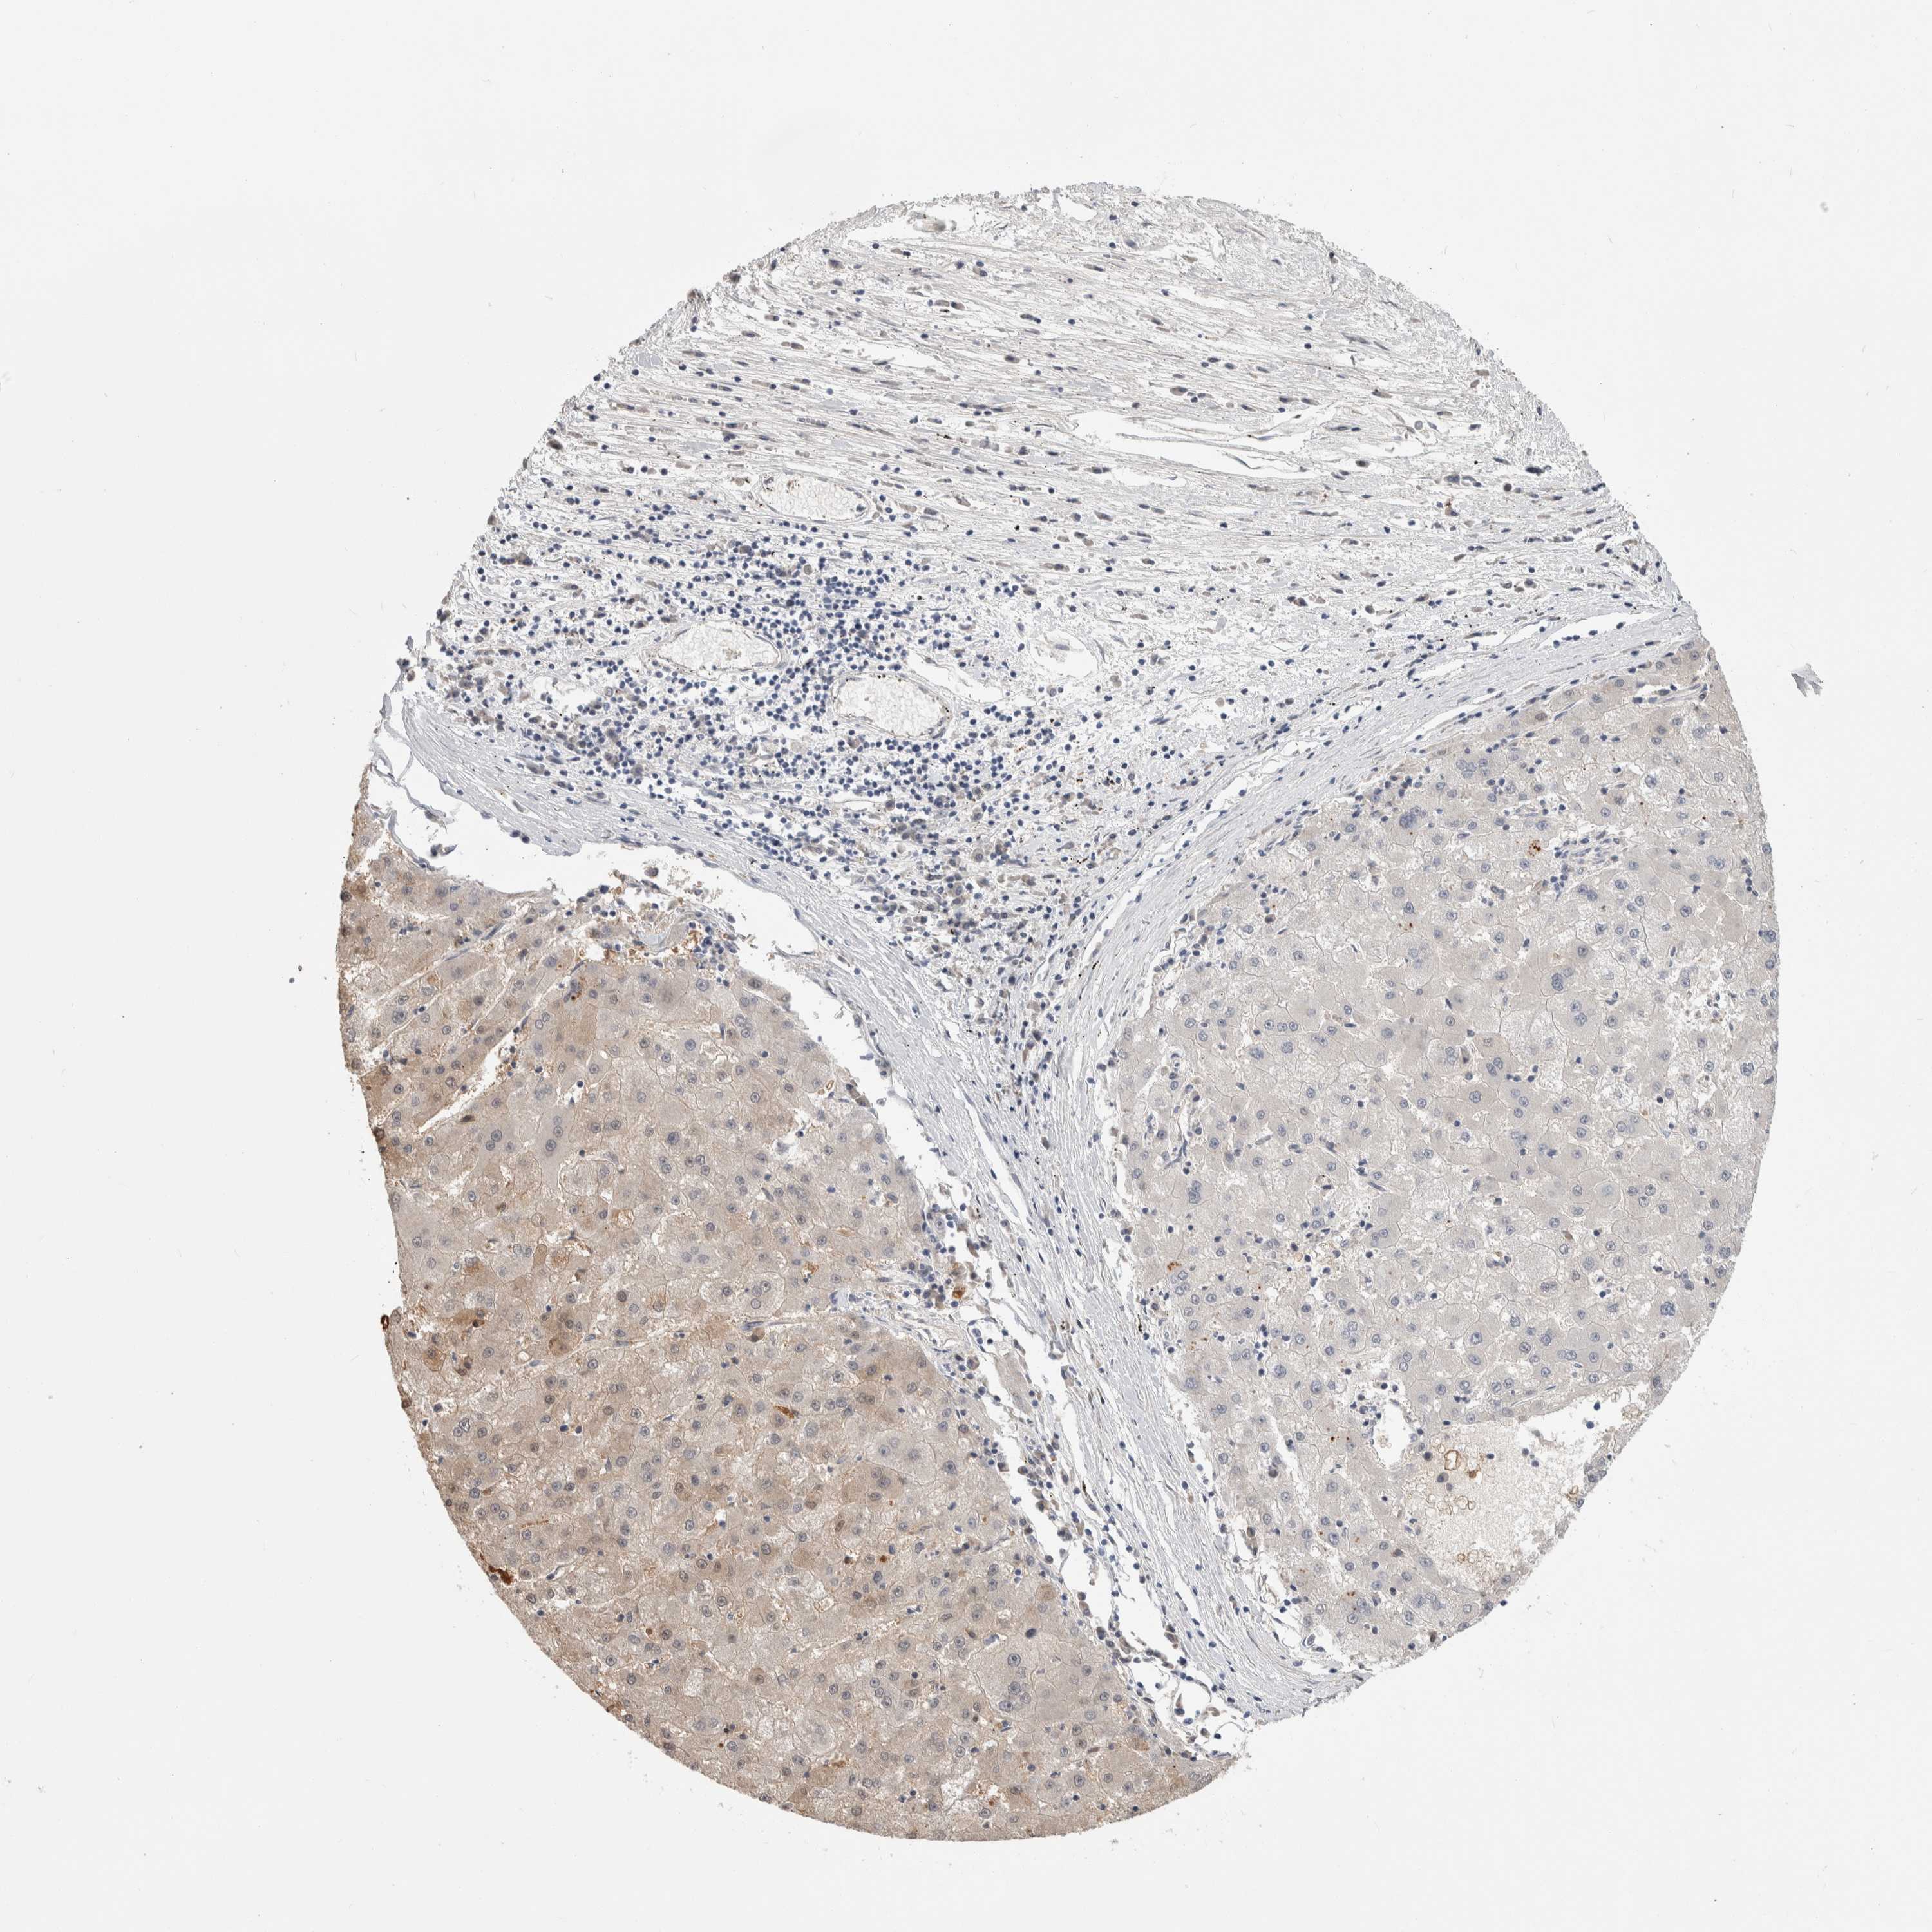

LIVER CANCER - Protein expressioni

A mouse-over function shows sample information and annotation data. Click on an image to view it in a full screen mode. Samples can be filtered based on level of antibody staining by selecting one or several of the following categories: high, medium, low and not detected. The assay and annotation is described here.

Note that samples used for immunohistochemistry by the Human Protein Atlas do not correspond to samples in the TCGA dataset.

Antibody stainingi

Antibody staining in the annotated cell types in the current human tissue is reported as not detected, low, medium, or high, based on conventional immunohistochemistry profiling in selected tissues. This score is based on the combination of the staining intensity and fraction of stained cells.

Each image is clickable and will lead to virtual microscopy that enables deeper exploration of all samples and also displays staining intensity scores, fraction scores and subcellular localization as well as patient and tissue information for each sample.

Antibody HPA024154

Staining

High

Medium

Low

Not detected

Intensity

Strong

Moderate

Weak

Negative

Quantity

>75%

75%-25%

<25%

None

Location

Nuclear

Cytoplasmic/membranous

Cytoplasmic/membranous,nuclear

Cholangiocarcinoma

Carcinoma, Hepatocellular, NOS